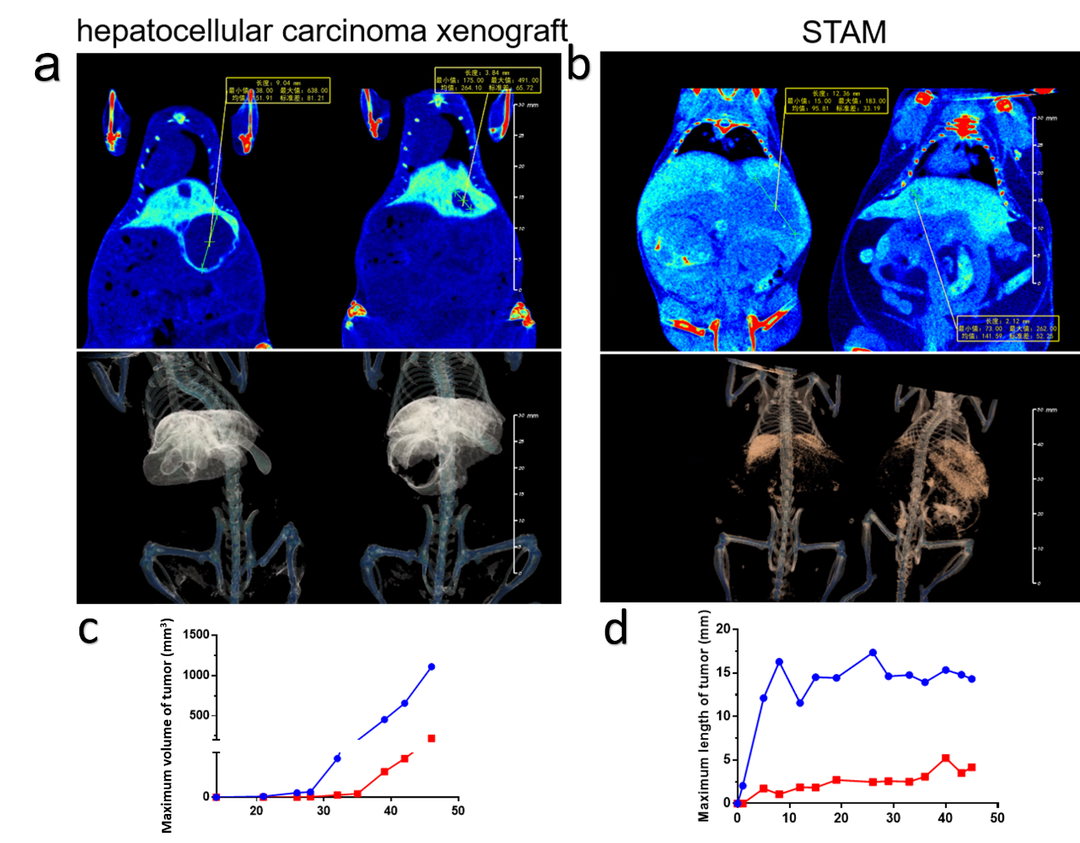

肝原位/STAM小鼠模型(In vivo)-肝肿瘤体积/最长径量化评价

Micro-CT检测肝肿瘤。(a)肝原位异种移植模型肿瘤示意图,黄色线段及方框内标注信息为实体瘤测量线段及长度,下方为3D渲染图像可在相同位置看到非肝细胞的肿瘤实质区域。(b)STAM模型肿瘤示意图黄色线段及方框内标注信息为实体瘤测量线段及长度,下方为3D渲染图像可在相同位置看到非肝细胞的肿瘤实质区域。(c,d) 肝原位肿瘤体积与STAM模型肿瘤最大长经统计图。